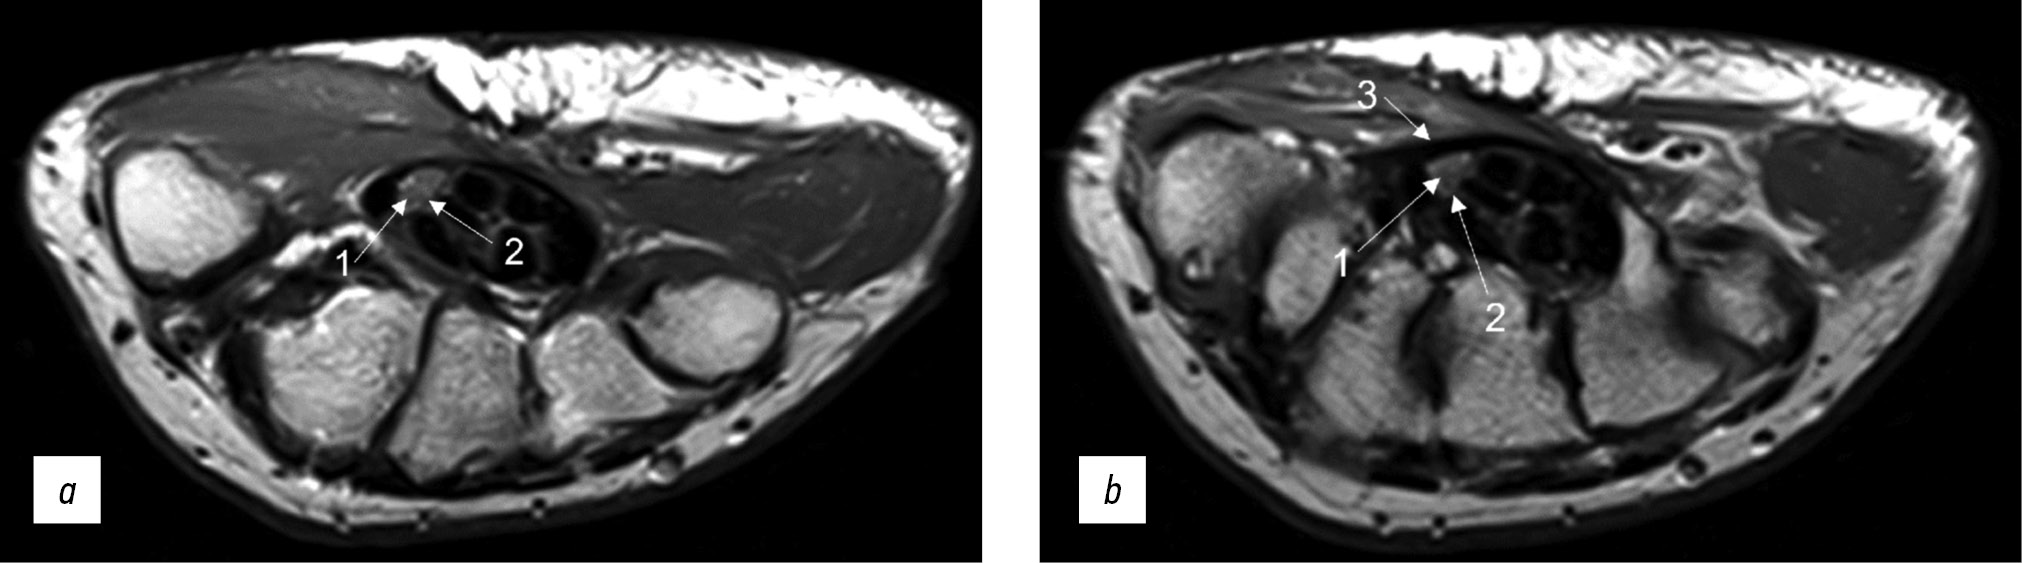

Early observations showed that T2 images are the most important for diagnosing peripheral nerve injuries [31]. Non-fat-suppressed sequences, typically 2D, are useful for observing the epineurium (Fig. 2). Fat suppression differentiates the relatively high nerve signal and the surrounding fat tissue. For T2-weighted images without fat suppression, the recommended echo time is >90 ms (milliseconds), ideally 100–105 ms. For fat-suppressed sequences, it can be reduced to 60–80 ms. The latter, so-called fluid-sensitive images, provide ideal nerve visualization (Fig. 3) with increased signals in the area of pathological changes [32]. Fat suppression strategies are based on the difference in water–fat precession frequency and fat tissue having a longer T2 relaxation time and shorter T1 relaxation time than muscle tissue or nerve fibers [2].

Fig. 2. Magnetic resonance imaging of the hand in T2 mode in a patient with carpal tunnel syndrome. An axial projection: (a) at the level of proximal epiphyses of metacarpal bonesand (b) at the level of distal parts of the capitate bone (1: individual fascicles as part of the median nerve, 2: epineurium, and 3: flexor retinaculum with a thickness of up to 1.29 mm).